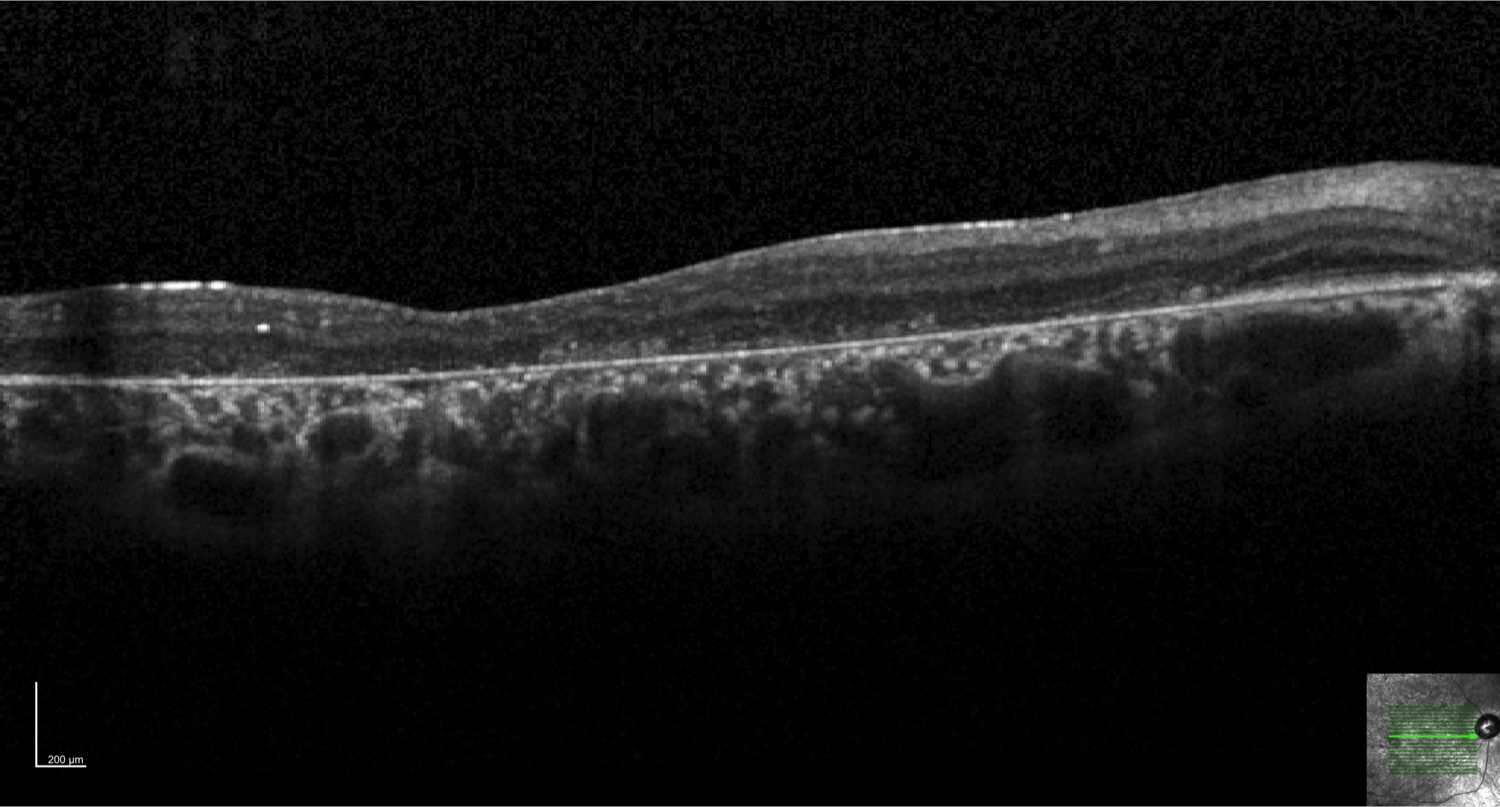

Case 11 is a 17 year old woman with 20/200 acuity. She had completely normal vision until about age 9. Her parents have normal acuity.

Optical coherence tomogram of the right eye.